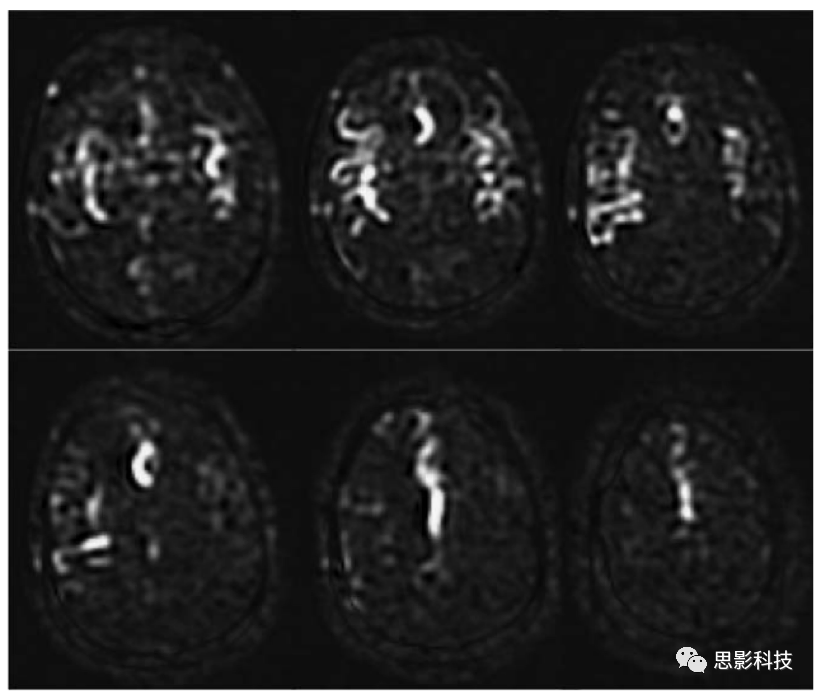

在默认情况下,本文不鼓励使用血流损毁梯度,因为它们可能会损失更多重要的临床信息,例如延迟血流和动静脉分流等。对于单PLD成像,选择PLD应使其在大多数情况下比ATT长。这种情况下,标记的灌注血流将在成像之前输送到目标组织,并且在成像时未标记的血液会进入较大的动脉。在这种情况下,血流损毁梯度法对ASL图像的影响将最小。然而,当ATT>PLD时,ASL图像中会出现明亮的血管信号,这些信号会被去除。对于某些应用,例如在侧支血流中,明亮的血管信号的存在可能是一个有用的指标,表明存在长ATT的区域,并且这些区域量化的CBF值可能有误;此信息本身可能也具有诊断价值。在动静脉畸形中,识别静脉中的ASL信号在临床上也有实际意义。如图7所示。

Figure 7 DSA图像血管位置与ASL图像高信号区域吻合性的对比

本文建议将血流损毁梯度为用户控制的选项,因为它的使用有一定的限制条件。对于诸如在肿瘤中的应用,明亮的血管内信号可能掩盖了感兴趣的更细微的潜在的与灌注相关的信号。如果时间允许,两次有无血流损毁梯度的ASL扫描可能提供更有用的信息。这些选择与ASL最终在临床环境中最终使用的方式有关。鼓励研究人员去应用上述技术来多次尝试。

如前所述,对于多PLD /TI成像,ATT可以在CBF之外进行估计。如果没有血流损毁梯度,测量的ATT将表示标记的血流到达体素的时间,而如果有血流损毁梯度,测量的ATT将反映出微血管系统中的到达时间。这些不同的ATT在不同的应用中应该有不同的用途。如果没有使用血流损毁梯度,应该考虑血液内部流动的影响,否则计算出的CBF可能不正确。

关于使用血流损毁梯度的另一条注意点是,当灌注成像作为组分析的一部分进行时,由于在如大动脉等不规则位置存在高强度斑点,因此血管伪影会使分析变得复杂,在这种情况下,可以考虑选择一定的血流损毁梯度。

血流损毁的特征可用VENC描述,或者说是流速引起相移的速度。粗略地说,自旋在VENC上方消除相位影响,并在VENC下方保持可见。很高的VENC可以保留大动脉信号,而非常低的VENC可以延长ATT并降低信噪比。在使用时,建议以4cm/s的VENC在PC-AC方向上进行血流损毁梯度采集,这是一个很好的折衷方案。

4、检查血管内伪影。高强度斑点和蛇形区域通常代表血管内信号。观察时,建议验证PLD是否适合患者,因为低PLD会自然在较大的动脉中产生ASL信号。具有正确PLD的动脉内信号表明,标记的血液通过缓慢的流动或间接的循环途径而延迟了向组织的输送。静脉ASL信号提示存在动静脉分流。请注意,如果不使用血流损毁梯度,则在存在血管内伪影的情况下,需要用整个大脑或较大目标区域的CBF计算。